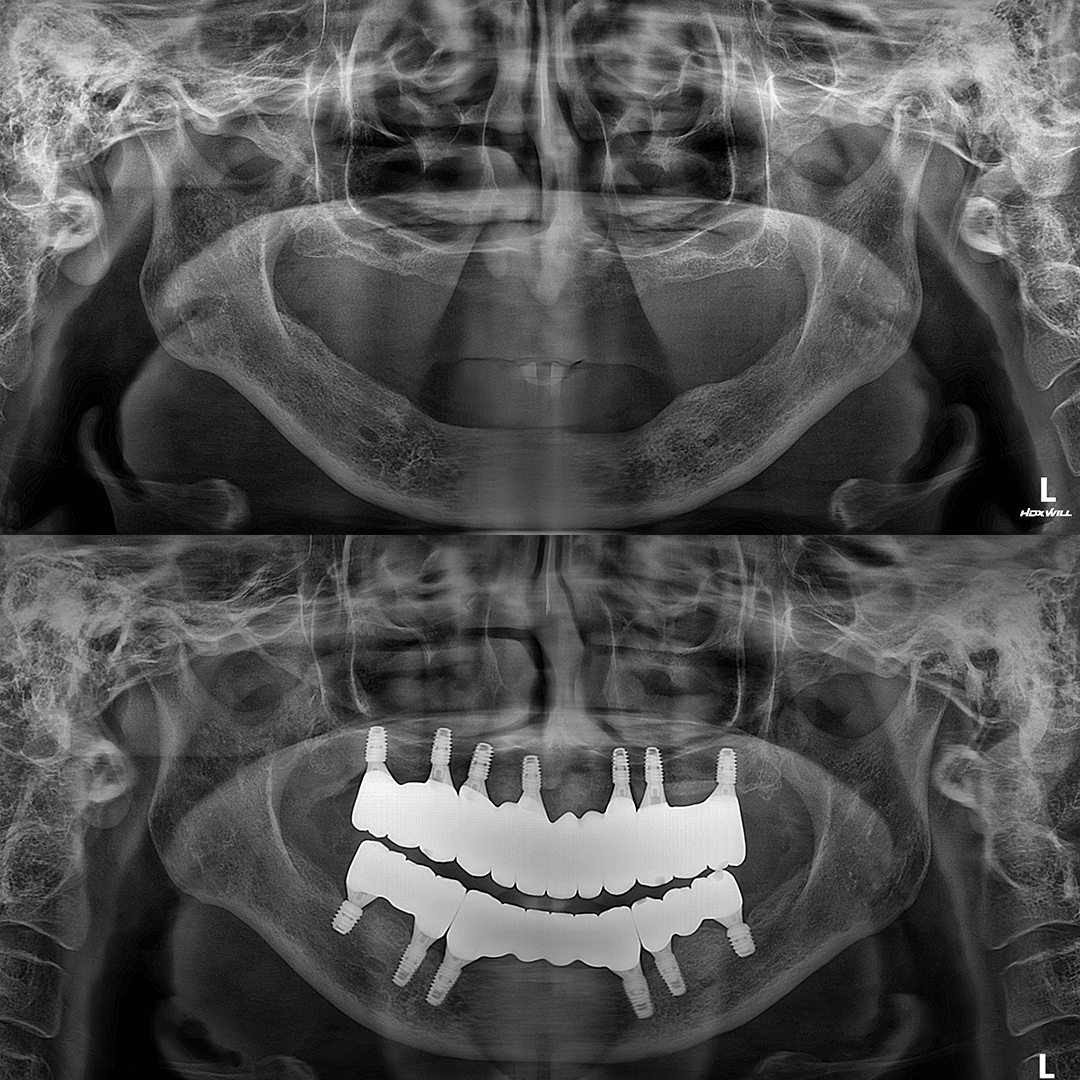

전체 임플란트

상·하악 전체 치아를 대체하는 임플란트로 최소한의 식립을 통해

자연치아와 비슷한 기능을 수행할 수 있도록 합니다.